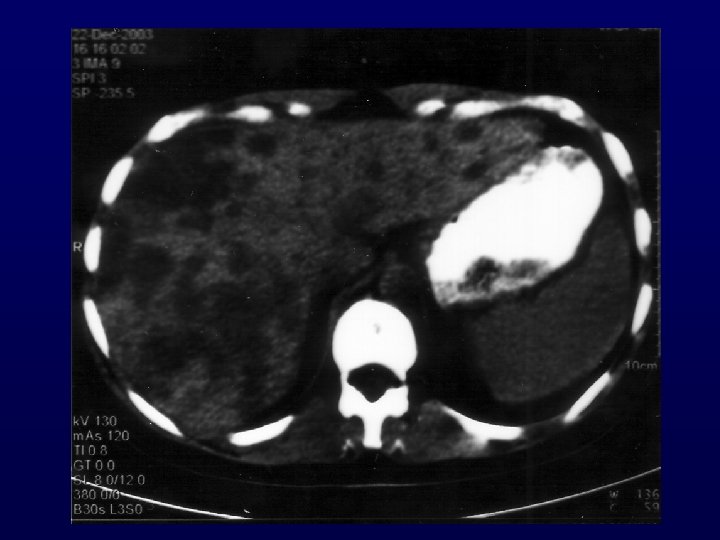

THE SUBSET OF ADENOCARCINOMA METASTATIC TO THE LIVER

HISTOLOGIC SPECTRUM OF LIVER METASTASES Histology Mousseau et al [Bull Cancer 1991] Ayoub et al [JCO 1998] Hogan et al [Clin Radiol 2002] Poussel et al Lazaridis et al [Gastr Clin Biol [Cancer Treat Rev 2005] 2008] Total (N= 91) (N=365) (N=88) (N=118) (N=49) (N=711) Adenocarcinoma 78% 61% 79. 5% 58% 69% Undifferentiated 12% 27% 3. 5% 20% 24% 20% Neuroendocrine - 9% 9% 14% 6% 9% Squamous 6% 2% 4. 5% 4% 0% 4% Others 4% 1% 3. 5% 4% - 3%

OVERALL RESULTS OF CHEMOTHERAPY IN CUP PATIENTS WITH LIVER METASTASES No of trials : 5 (1991, 1998, 2002, 2005, 2008) No of patients : 711 Response rate : < 20% Median survival : 5. 5 months Bull Cancer 1991, J Clin Oncol 1998, Clin Radiol 2002, Gastroent Clin Biol 2005, Cancer Treat Rev 2008